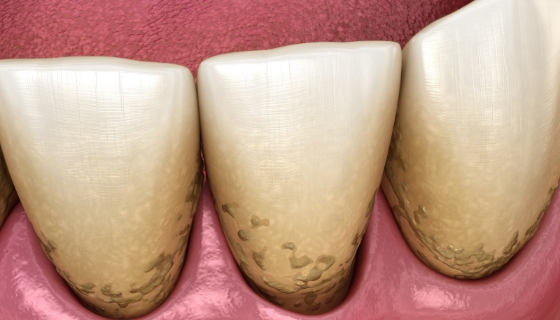

むし歯になる三大要素

- 細菌

- 虫歯の原因となる細菌の活動を抑える働きを持つキシリトールやフッ化物を活用したり、歯科医院でのメンテナンスで菌の塊である歯垢(プラーク)を除去しましょう。